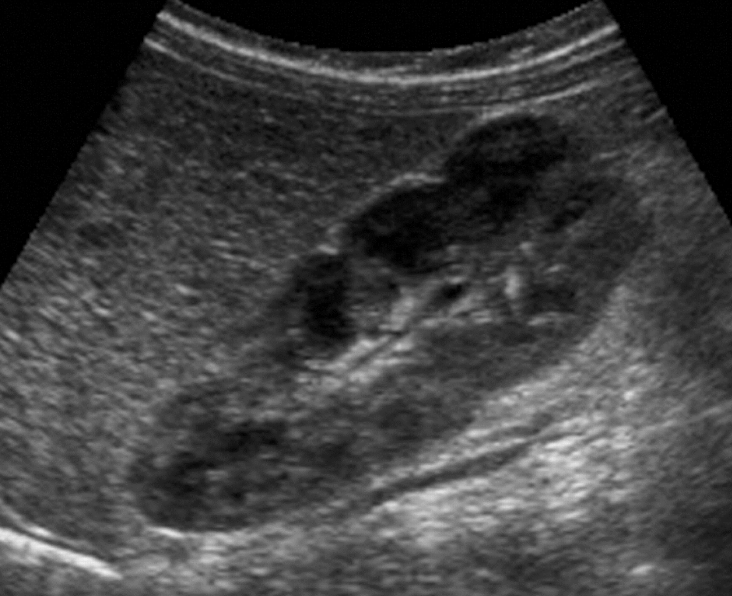

SONO: renal cell carcinoma (RCC)

isoechoic or hyperechoic

solid or cystic

intratumoral calcification

hypoechoic rim (represents vascular pseudocapsule on color Doppler)

MC vascular patterns is “basket sign” and/or “vessels within tumor”

?invasion of the renal vein and IVC

RCC can invade what vessels?

renal vein and IVC

?? describe

RCC

“isoechoic solid circumscribed structure noted in MP/LP of RK measuring 3 cm x 3 cm x 3 cm. difficult to determine border”